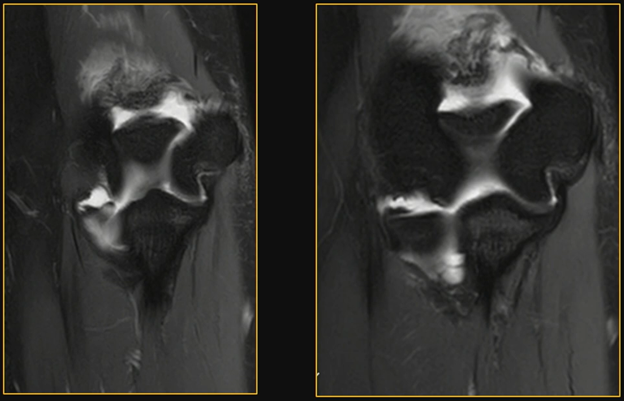

Little Leaguer’s Elbow: Clinical Catch-All

The most common manifestation is medial epicondyle apophysitis, an injury occurring during the acceleration phase of pitching when valgus stress creates significant medial traction.